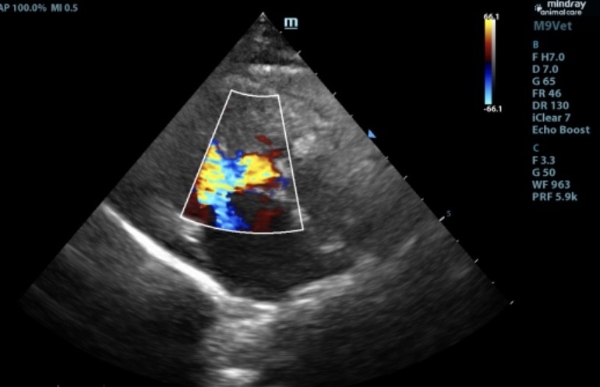

心脏科:精细检测,守护每次心跳

心脏疾病是老年宠物常见的健康问题,医院配备了进口心脏彩超设备,能够精准诊断各种心脏疾病。负责心脏科的张培培医生擅长心肌病、肥厚型心肌病等复杂心血管疾病,并提供长期药物管理和定期随访服务,帮助宠物维持良好的心脏功能。

此前,6岁的猫咪因抽搐呕吐,后腿无力就诊,经查后发现左心室心肌及室间隔厚度增加,主动脉和二尖瓣均存在反流,诊断为肥厚型心肌病。口服利尿剂和抗血栓药物,一周后精神好转,再无出现抽搐、呕吐、后腿无力等现象。